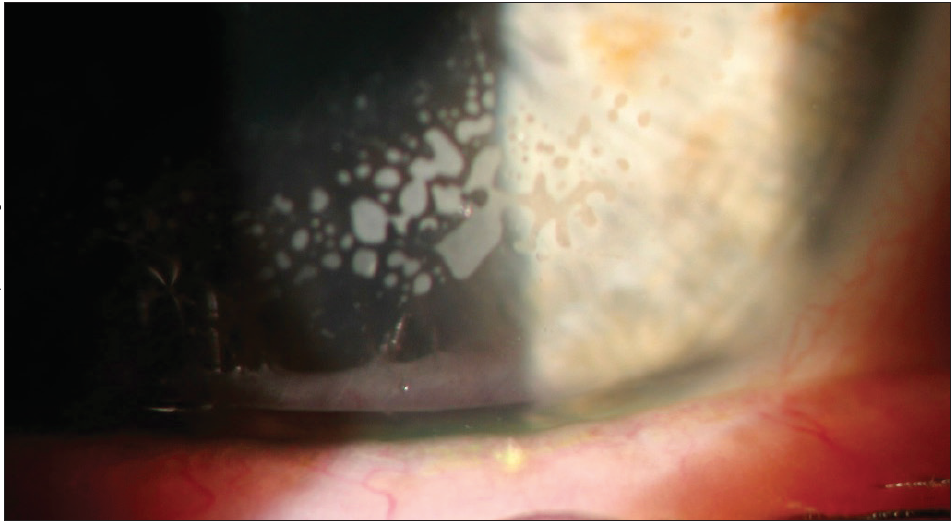

After LASIK, epithelial cells can migrate between the corneal flap and the stromal bed. Epithelial ingrowth typically occurs during the first 3 months after surgery, often in the first 1 to 2 weeks. The patient may experience a decrease in vision secondary to astigmatic changes from topographic alterations produced by the invading cells. A diagnosis is usually made during the slit-lamp examination, which reveals pearly white aggregates with a smooth outline (Figure 1). Nests of cells that cause whorl-like opacifications can also appear, usually close to the flap’s edge.

Figure 1. Epithelial ingrowth noted upon slit-lamp examination. Intralamellar epithelial cells with a whorl-like pattern, as seen here, are key to identification.

If the epithelial ingrowth is located away from the visual axis or pupil, the patient may be observed, and the complication may resolve on its own. If the epithelial ingrowth is visually significant or larger than 2 mm, then surgical intervention is required. This typically involves lifting the flap, scraping the epithelial cells, and placing a bandage contact lens.